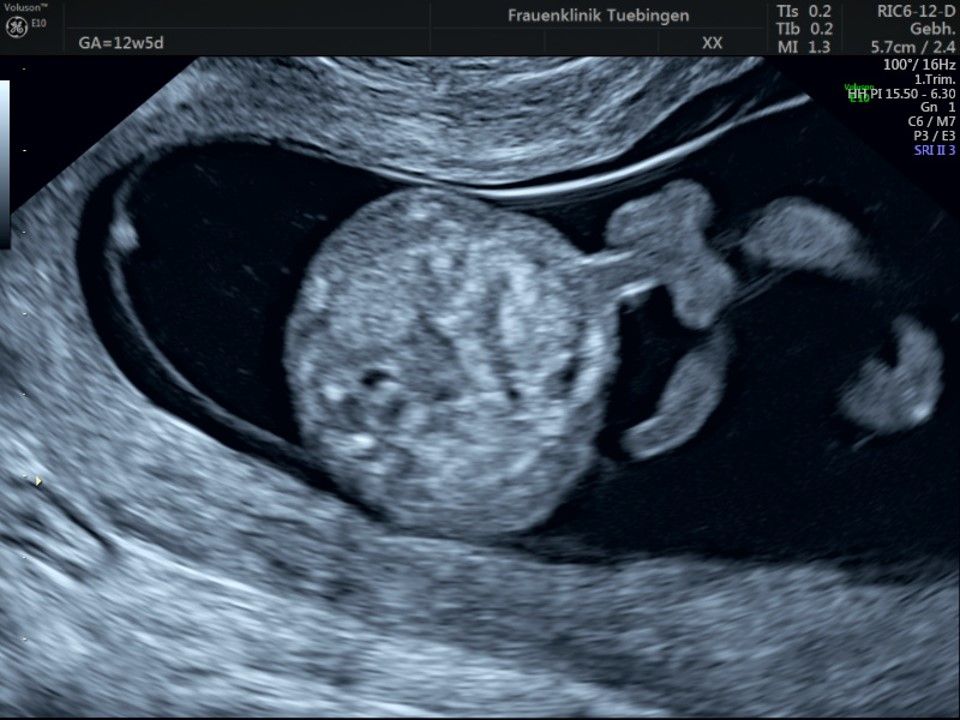

Im Rahmen des Ersttrimester-Screenings untersuchen wir die Organe des Feten mittels Ultraschall. Dabei machen wir auch gerne ein Bild für Sie.

Obwohl der Fet zu diesem Zeitpunkt erst zwischen 5 und 8cm groß ist, lassen sich bereits etwa die Hälfte aller schwerwiegenden Fehlbildungen erkennen bzw. ausschließen. Sollten wir eine Auffälligkeit sehen, werden wir mit Ihnen den Befund und das weitere Vorgehen ausführlich besprechen.

Das Ergebnis der Ultraschalluntersuchung ist wegweisend. Dabei wird der Fet vermessen, die Organe werden untersucht und die sonographischen Marker zur Risikoberechnung für Chromosomenstörungen werden beurteilt. Das sind: die Nackentransparenzdicke, Nasenbein sowie der Blutfluss in der rechten Herzhälfte und im Ductus venosus, einem Gefäß in der Leber des Feten.